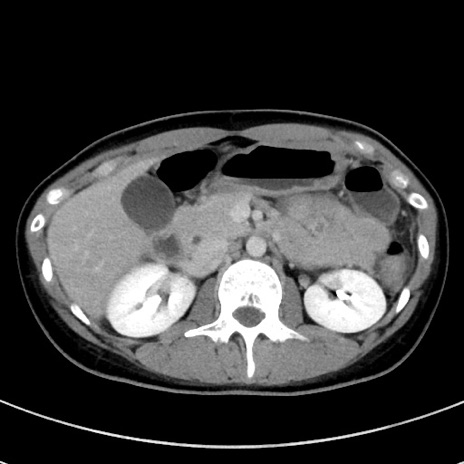

症例17(横断像)

【症例】20歳代女性

【主訴】嘔吐、下腹部痛

【現病歴】昨日夕食後に嘔吐し下腹部痛が出現。本日になっても嘔吐持続し改善しないため来院。

【身体所見】意識清明、BT 37.2℃、BP 108/67mmHg、腹部:平坦、やや硬、下腹部正中から右にかけて圧痛あり、反跳痛軽度あり、tapping pain(+)。

【データ】WBC 13600、CRP 14.94